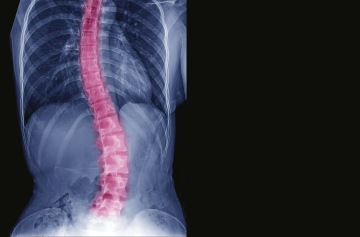

Skolióza je strukturální deformita páteře v 3D prostoru. Tzn., že páteř je vychýlená předozadně, do strany a obratle jsou rotovány a deformovány. Na to dále navazuje změna tvaru hrudníku a žeber. Jedná se o poměrně závažné postižení, které komplexně ovlivňuje nejen pohybový aparát, ale také naše orgány, hlavně kardiopulmonární systém.

Skoliózu nejčastěji poznáme když se pacient předkloní a jedna strana zad zůstává vystouplejší než druhá. Přesnou diagnózu určí až RTG snímek páteře, který ukáže také míru postižení podle velikosti zakřivení tzv. Cobbova úhlu. O skolióze mluvíme tehdy, pokud je úhel větší než 10 stupňů.